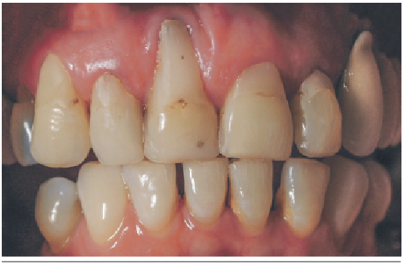

Se presenta el caso clínico de una paciente sana género femenino de 60 años. Sin antecedentes de alergias ni consumo de tabaco. Al examen clínico se evidencia una extensa recesión RT1 de Cairo11 clase B -12 en relación al diente 1.1 de 6 mm, el cual presentaba una restauración cervical con composite y movilidad tipo 1. Figura 2. Al examen imagenológico se evidencia una pérdida total de la tabla vestibular y una parte del hueso en relación al ápice de diente. Figura 3. La indicación inicial fue la regeneración ósea y la planificación de un implante. No obstante, la falta de tejido blando y duro en vestibular, hicieron que fuera estéticamente imposible, ya que correspondía a una clase 3 de Elian por lo que no fue posible realizar una técnica de “Ice cream cone”1 y/o la instalación del implante simultáneamente2. Por lo que fue necesario regenerar primero el tejido blando y transformar de una clase 3 a una clase 2. Figura 4.